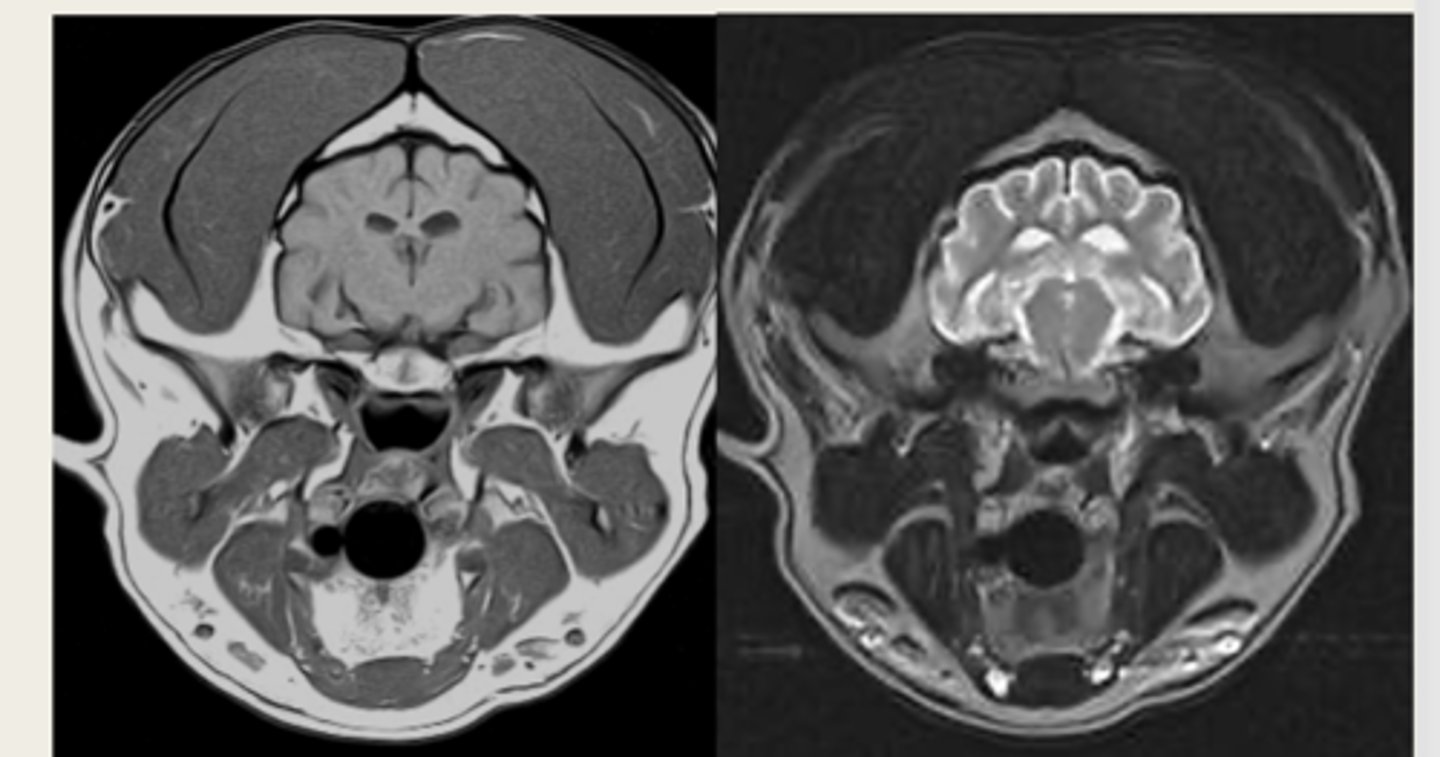

-T1 weighted

-T2 weighted

what are the two main MRI sequences?

left- T1 weighted

right- T2 weighted

which image is T1 weighted and which is T2 weighted?

anatomy

T1 weighted images are good for ________

pathology

T2 weighted images are good for identifying __________

hyperintense

Pathologic tissues such as tumors or areas of inflammation are "juicy" so they are what intensity?

left- T1 weighted

right- T2 weighted

which MRI image is T1 or T2 weighted?